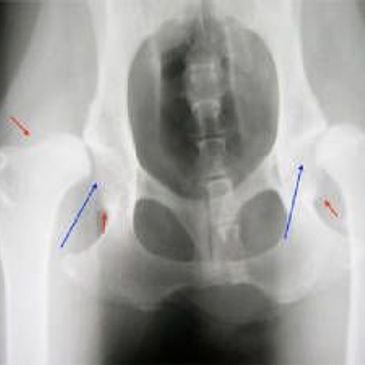

We offer hip and elbow radiology scoring.